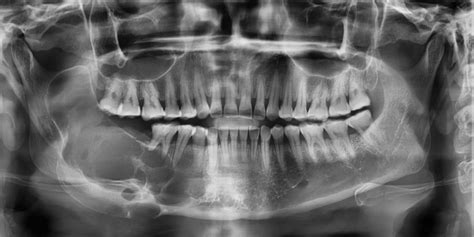

Generalmente es necesario realizar una radiografía para diagnosticar esta patología que se manifiesta a través de una zona oscura en el hueso. En la ortopantomografía (radiografía en 2D de toda la boca) el quiste maxilar se observa como una zona oscura y redondeada en forma de bolsa.

El principal método para detectar un quiste maxilar es a través de una radiografía, en la que se puede observar una mancha de color oscuro en el hueso. Una vez que el dentista sepa de la presencia del quiste, es posible que solicite pruebas adicionales, tales como una tomografía computarizada o una biopsia, que le permitan tener una información más completa y detallada sobre el tipo de quiste, la extensión del mismo y sus características.

Antes de realizar cualquier tratamiento dental es fundamental realizar un buen diagnóstico. Este debe incluir un estudio clínico y radiográfico previo, para poder determinar la extensión de la patología y clasificarlo según sus características.